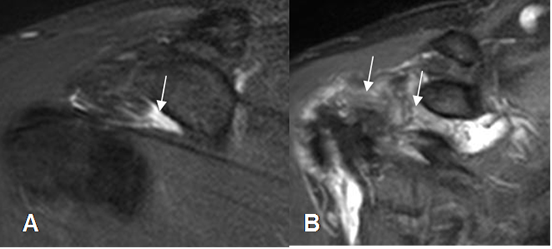

Fig 23. Ligamento glenohumeral superior normal.

A: RM axial en FFE y B: ArtroRM axial. Ligamento GHS normal.

Fig 24. Ligamento glenohumeral medio normal.

A: RM axial en FFE. Ligamento normal entre el labrum anterior y el tendón del subescapular.

B: ArtroRM axial y C: ArtroRM sagital en STIR. Ligamento GHM normal.

Fig 25. Ausencia del ligamento glenohumeral medio.

ArtroRM axial en STIR. No visualización del LGHM, por ausencia congénita. Tendón del subescapular normal. (Flecha).

Fig 26. Ligamento glenohumeral inferior normal.

A: ArtroRM axial y B: ArtroRM coronal. Banda anterior del ligamento GHI normal.

C: ArtroRM sagital. Banda anterior (Flecha delgada) y banda posterior (Flecha gruesa) normales.